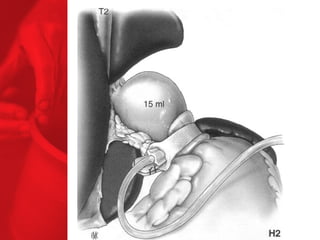

ANNEAU GASTRIQUE AJUSTABLEProcédure restrictive SAGB ® (anneau gastrique ajustable suédois) forme d'un sablier l'opération inverse peut être effectuée la digestion et l'absorption sont normales, aucun effets secondaires de la malabsorption moyenne de surcharge pondérale à 3, 4 et 5 ans après l'étude : 49, 55 et 57% respectivement* diminue le diabète de type 2 chez près de 77% des patients** *Laparoscopic SAGB: a 5-year Prospective Study, R. Steffen et al, Obesity Surgery, 13, 2003, 404-411 **Buchwald H, Avidor Y, Braunwald E, et al. Bariatric Surgery—A Systematic Review of the Literature and Meta-analysis. Journal of the American Medical Association 2004 Oct 13;292(14).

COMMENT FONCTIONNE L'ANNEAUGASTRIQUE AJUSTABLE ? Facteurs chirurgicaux Restriction du volume des repas Un sentiment de satiété plus tôt et pendant plus longtemps Restriction plus haute ou plus basse grâce au règlage de l'anneau Facteurs pour les patients Apport en calories voué à l'échec par une mauvaise nourriture et mauvais liquides dépense en calories BILAN ENERGETIQUE = apport alimentaire dépense en énergie

ANNEAU GASTRIQUE AJUSTABLE Procédure restrictive SAGB ®  (anneau gastrique ajustable suédois) forme d'un sablier l'opération inverse peut être effectuée la digestion et l'absorption sont normales, aucun effets secondaires de la malabsorption moyenne de surcharge pondérale à 3, 4 et 5 ans après l'étude :   49, 55 et 57% respectivement* diminue le diabète de type 2 chez près de 77% des patients** *Laparoscopic SAGB: a 5-year Prospective Study,  R. Steffen et al, Obesity Surgery, 13, 2003, 404-411 **Buchwald H, Avidor Y, Braunwald E, et al. Bariatric Surgery—A Systematic Review of the Literature and Meta-analysis. Journal of the American Medical Association 2004 Oct 13;292(14).